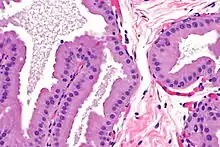

Apocrine metaplasia

Micrograph showing apocrine metaplasia of the breast. H&E stain.

Apocrine metaplasia is a reversible transformation of cells to an apocrine phenotype. It is common in the breast in the context of fibrocystic change. It is seen in women mostly over the age of 50 years. Metaplasia happens when there is an irritation to the breast (breast cyst). Apocrine-like cells form in a lining of developing microcysts, due to the pressure buildup within the lumen. The pressure build up is caused by secretions.[4] This type of metaplasia represents an exception to the common rule of metaplasia increasing the risk for developing cancer in that apocrine metaplasia doesn't increase the possibility of developing breast cancer.[5]